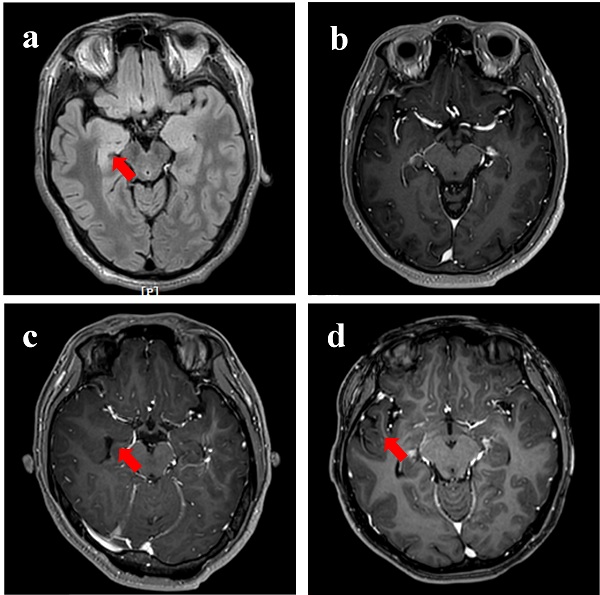

本工作首先收集了5位难治性癫痫病人病灶组织。术前磁共振图像显示有三位患者无明显异常病灶(图1)。免疫荧光染色结果显示癫痫病灶处血管内皮细胞间紧密连接蛋白(ZO-1)表达相对完整,且血管内皮细胞、活化星型胶质细胞以及小胶质细胞上LRP1表达较正常脑组织显著升高(图2)。

图1. 耐药性癫痫患者的代表性MR图像。(a)30岁男性,其右海马体中有高强度的T2信号。(b)32岁男性,给予Gd3+-DTPA后,T1W MR图像中无信号增强。(c)21岁女性,给以Gd3+-DTPA后,右海马无明显T1W信号增强。(d)25岁女性,给予Gd3+-DTPA后,右颞叶侧未检测到明显T1W信号增强。红色箭头指示切除癫痫灶。